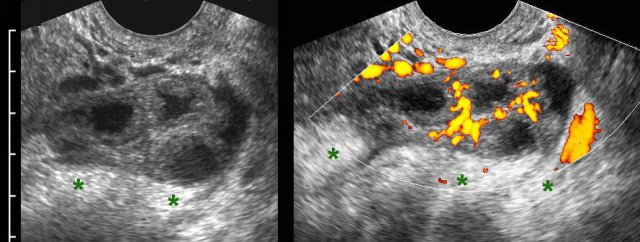

TOA case 1

Young,

very ill woman with acute LLQ pain and a CRP of 260. Left of the uterus a massively

enlarged (6 x 7 x 8 cm) ovary is found.

The individual follicles are enlarged, ill-defined

and filled with turbid fluid (pus).

Note the hyperechoic halo around this inflamed

mass.

Since

there is no apparent involvement of the Fallopian tube, strictly speaking this

is an oophoritis.

Nevertheless, usually the term of tubo-ovarian abscess is used.